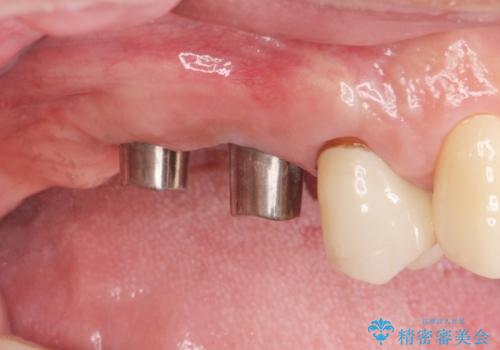

- 歯を抜いたまま放置してしまい、「やはりしっかりと噛めるような状態にしてほしい」とインプラント治療を希望され来院されました。

人工歯根であるインプラントを埋入することで奥歯でまたしっかりと噛める咬合機能を回復します。

- 88万円(インプラント×2・仮歯×2・チタンカスタムアバットメント×2・ジルコニアクラウン×2)費用は治療当時の料金となります